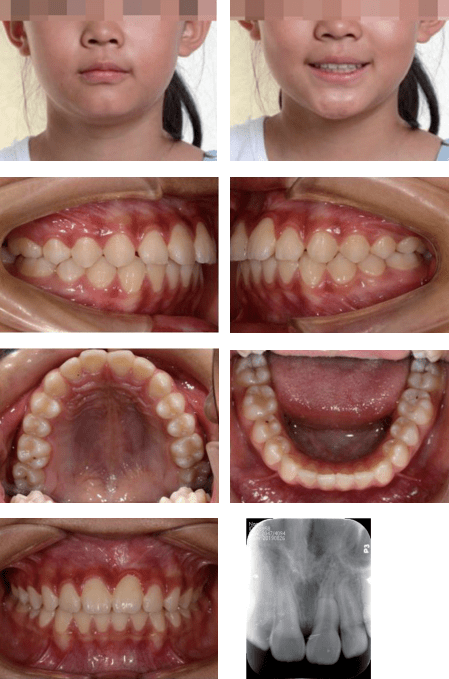

埋伏阻生弯曲中切牙的多学科治疗——王秀婧副主任医师_牙根